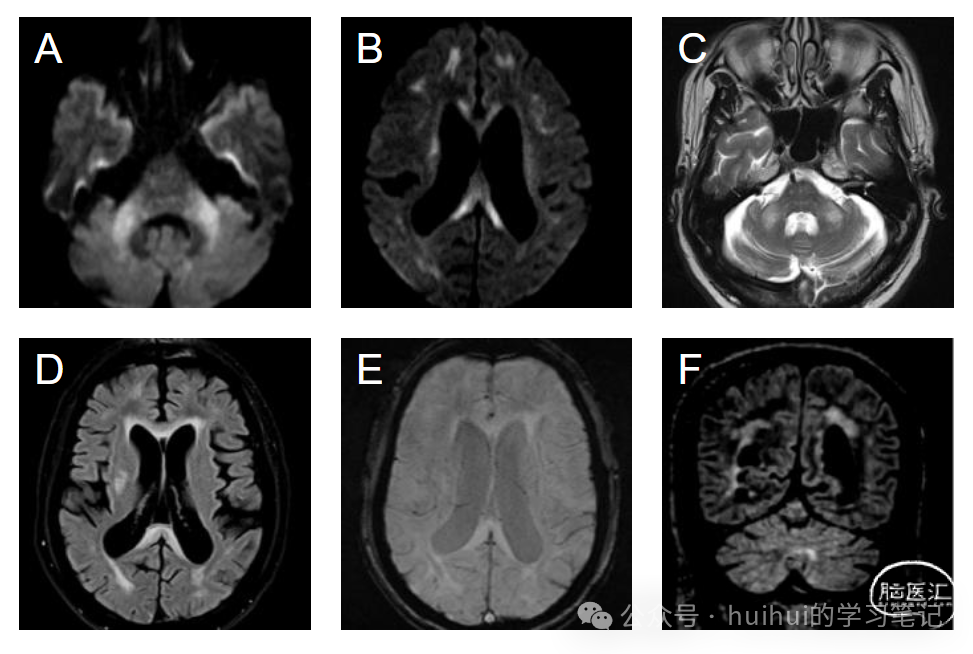

● FXTAS最常见的特征是MCP征(小脑中脚T2高信号),见于60%的男性患者和13%的女性患者。

● 第二个主要影像学特征是胼胝体压部T2高信号,与MCP征一样常见,也更常见于男性。FLAIR高信号可见于小脑的椎旁区域。

● 其他影像学特征:脑桥、岛叶、脑室周围白质T2高信号,弥漫性脑和小脑萎缩,小脑上、中脚、大脑脚、穹窿、终纹各向异性分数明显降低。